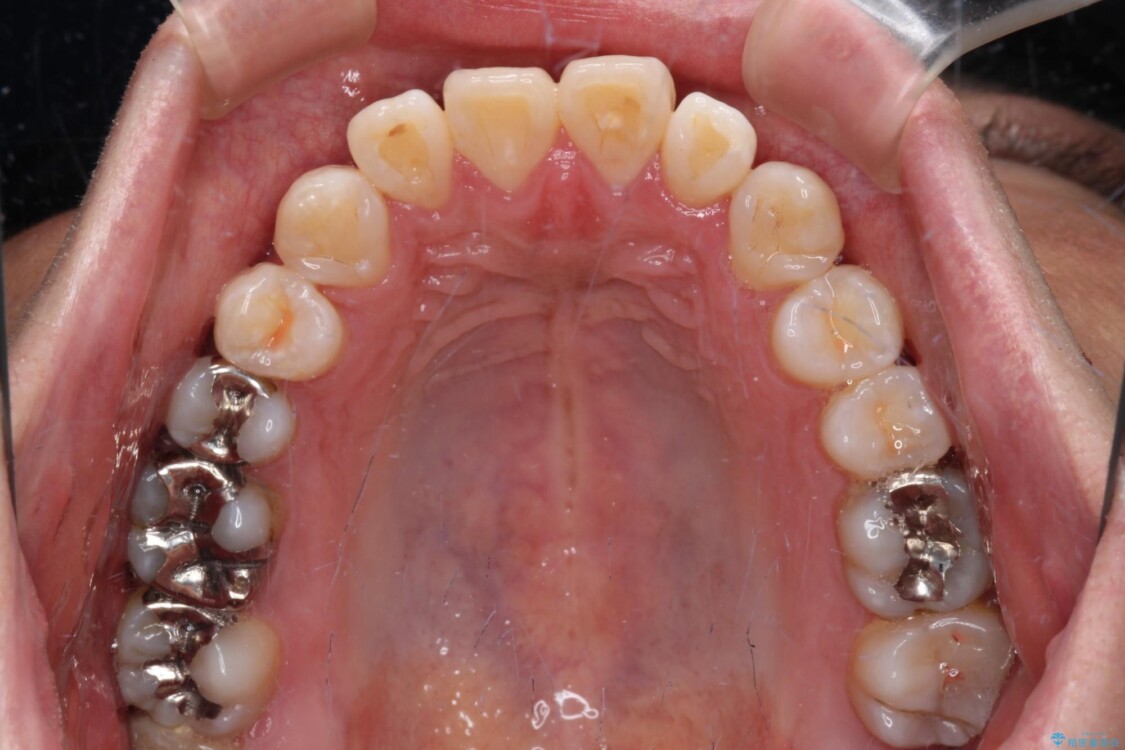

治療前

• 口元の突出感を改善!目立ちにくいワイヤー矯正で自信を持てる自然な横顔に 治療前画像

精密検査の結果、上下左右の小臼歯4本を抜歯し、そのスペースに前歯を後方へ移動させる矯正治療をご提案しました。

装置は、透明感のあるクリアブラケットとホワイトコーティングされたワイヤーを使用した、目立ちにくい審美装置を選択。

周囲に気づかれにくく、日常生活にも自然に溶け込みます。